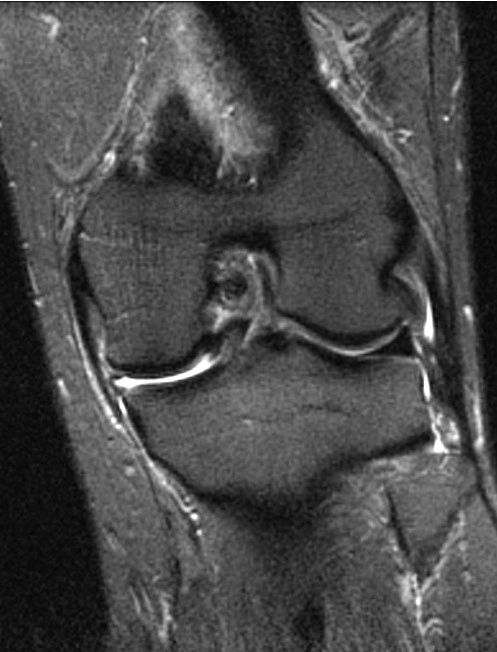

Rách dây chằng chéo trước ACL (Anterior cruciate ligament tear)

Rách dây chằng chéo trước (ACL) mạn tính

Rách dây chằng chéo sau (Posterior Cruciate Ligament - PCL tear)

Tổn thương góc sau ngoài ở khớp gối (Posterolateral corner injury of the knee)

Tổn thương góc sau trong (Posteromedial corner injury of the knee)